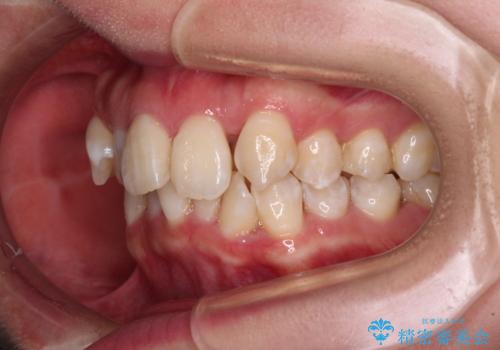

- 前歯1本が後ろ側に隠れてしまうほどのデコボコを気にして来院された患者様です。

前歯のデコボコが顕著なのはもちろんですが、左右ともに奥歯の咬み合わせに問題があり、上顎臼歯が前方位にある状態でした。

上顎は左右の第一小臼歯2本を、下顎は左右第二小臼歯2本を抜歯することで、奥歯の咬み合わせを改善しながら、デコボコを解消していくこととしました。